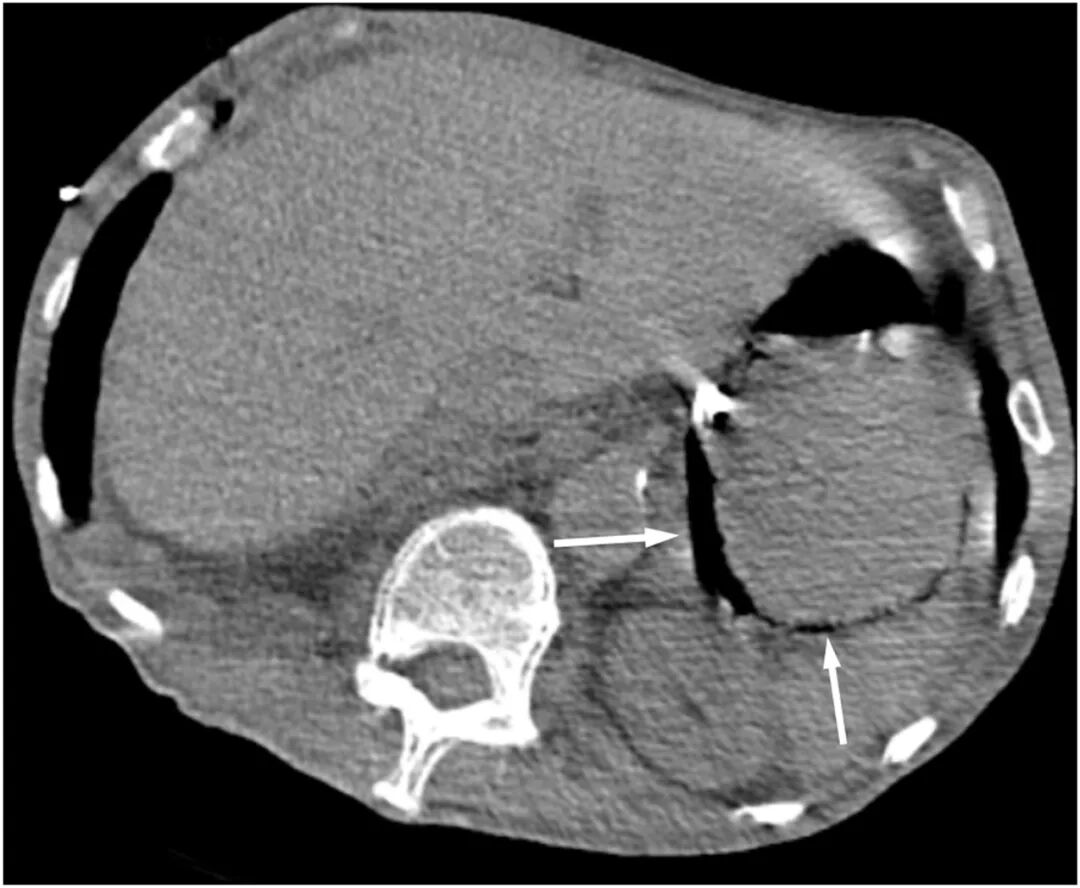

ICU第6日,患者因肠内营养不耐受出现轻微腹胀,C反应蛋白升高(199.69 mg/L),提示感染加重。鉴于病情变化,行床边即时超声检查,显示胃壁内出现“彗星尾”伪影(见图2、图3)。随后行腹部CT证实胃壁内气体积聚(图4)。

图4 腹部CT显示胃壁黏膜下积气(箭头)

胃壁内气体的存在是气肿性胃炎的关键影像学特征,通常可通过腹部CT得以明确。CT扫描能够清晰显示胃壁内的低密度线性影,有助于区分气肿性胃炎和良性胃气肿 。本病例中,在CT确诊前,通过床旁超声检查率先捕捉到了胃壁的“彗星尾征”伪像,这一发现为早期诊断提供了宝贵线索。“彗星尾征”通常与肺部和胆囊疾病相关。